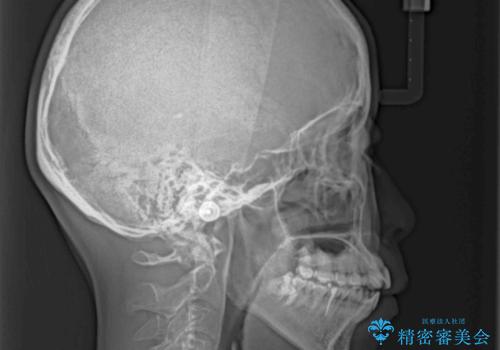

- 上下前歯が非接触となり、前方に突出していることを気にして来院された患者様です。

上下の前後差が大きいため、インビザライン単独での上顎歯列移動は困難と判断し、補助装置により上顎歯列を後方移動させ、その後インビザラインにて仕上げていくこととしました。

また、舌の突出癖が非接触の原因の大きな要因と考えられるため、舌のトレーニングをしっかり行っていくよう指導しました。